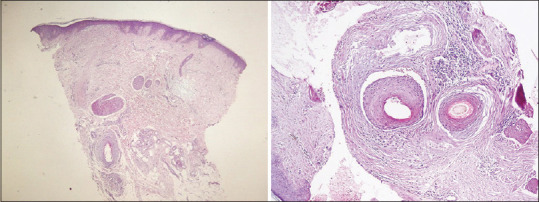

Background: Lichen planopilaris (LPP) is an inflammatory disease that results in destruction of the hair follicle and replaces it with patchy permanent scarring alopecia; after stabilizing by treatment, reactivation is common and may be insidious. During remission, various methods are available for realizing that the disease is activated or not, but neither of them is practical for patients.

Patients and methods: In a prospective study, during 2 years, 83 treated LPP patients have been divided into two groups of 41 and 42. Group 1 instructed for paper sign test which is to comb their hair over a white paper sheet to catch any fallen hairs, then turn the paper upside down, if all collected hair on paper completely separated, test is considered negative, if even one hair hangs onto the paper, the test is considered positive. Group 2 trained for clinical symptoms (hair shedding, scaling, itching, pain, tenderness, and burning).

Results: From the first group, 13 patients had positive paper sign, and from the second group, 35 patients had clinical symptoms; after clinical examination and biopsy, 13 from Group 1 and 17 from Group 2 were confirmed to have reactivated disease. Patients in the first group who had been trained for paper sign test became aware of relapse sooner and came earlier for the evaluation of disease.

Conclusion: Paper sign test is a reliable, noninvasive, and practical test for early detection of reactivated LPP by patients during remission period.